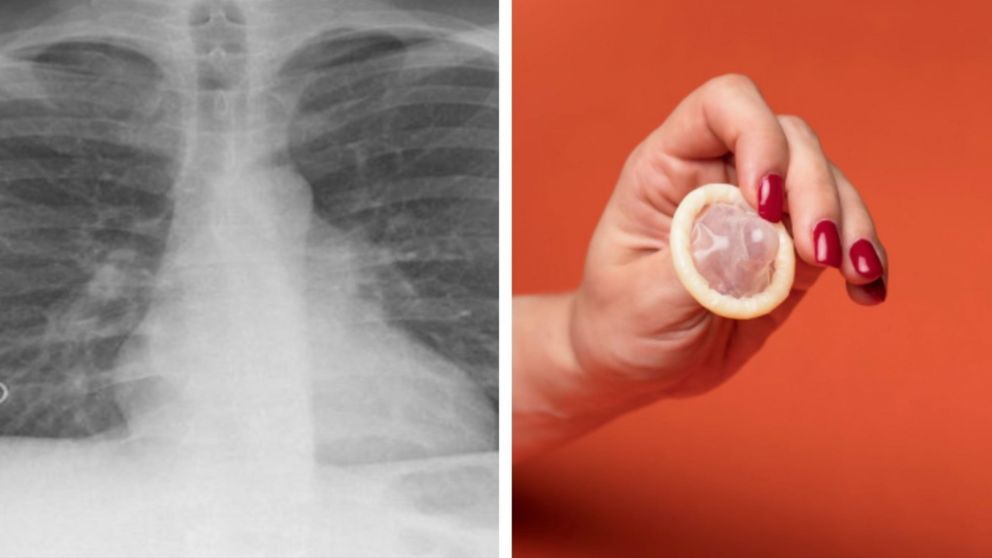

Maestra fue al hospital para atenderse de tuberculosis y le encontraron un preservativo en los pulmones

Una radiografía de su pecho reveló una lesión en el lóbulo superior derecho de sus pulmones, que parecía tener "una estructura en forma de bolsa invertida asentada en el bronquio", indicaron los especialistas, que tras una intervención quirúrgica extrajeron la misteriosa "bolsa".

Aunque la mayor parte de la misma fue destruida en todo el proceso, se comprobó que en realidad lo que provocó todo fue un preservativo.